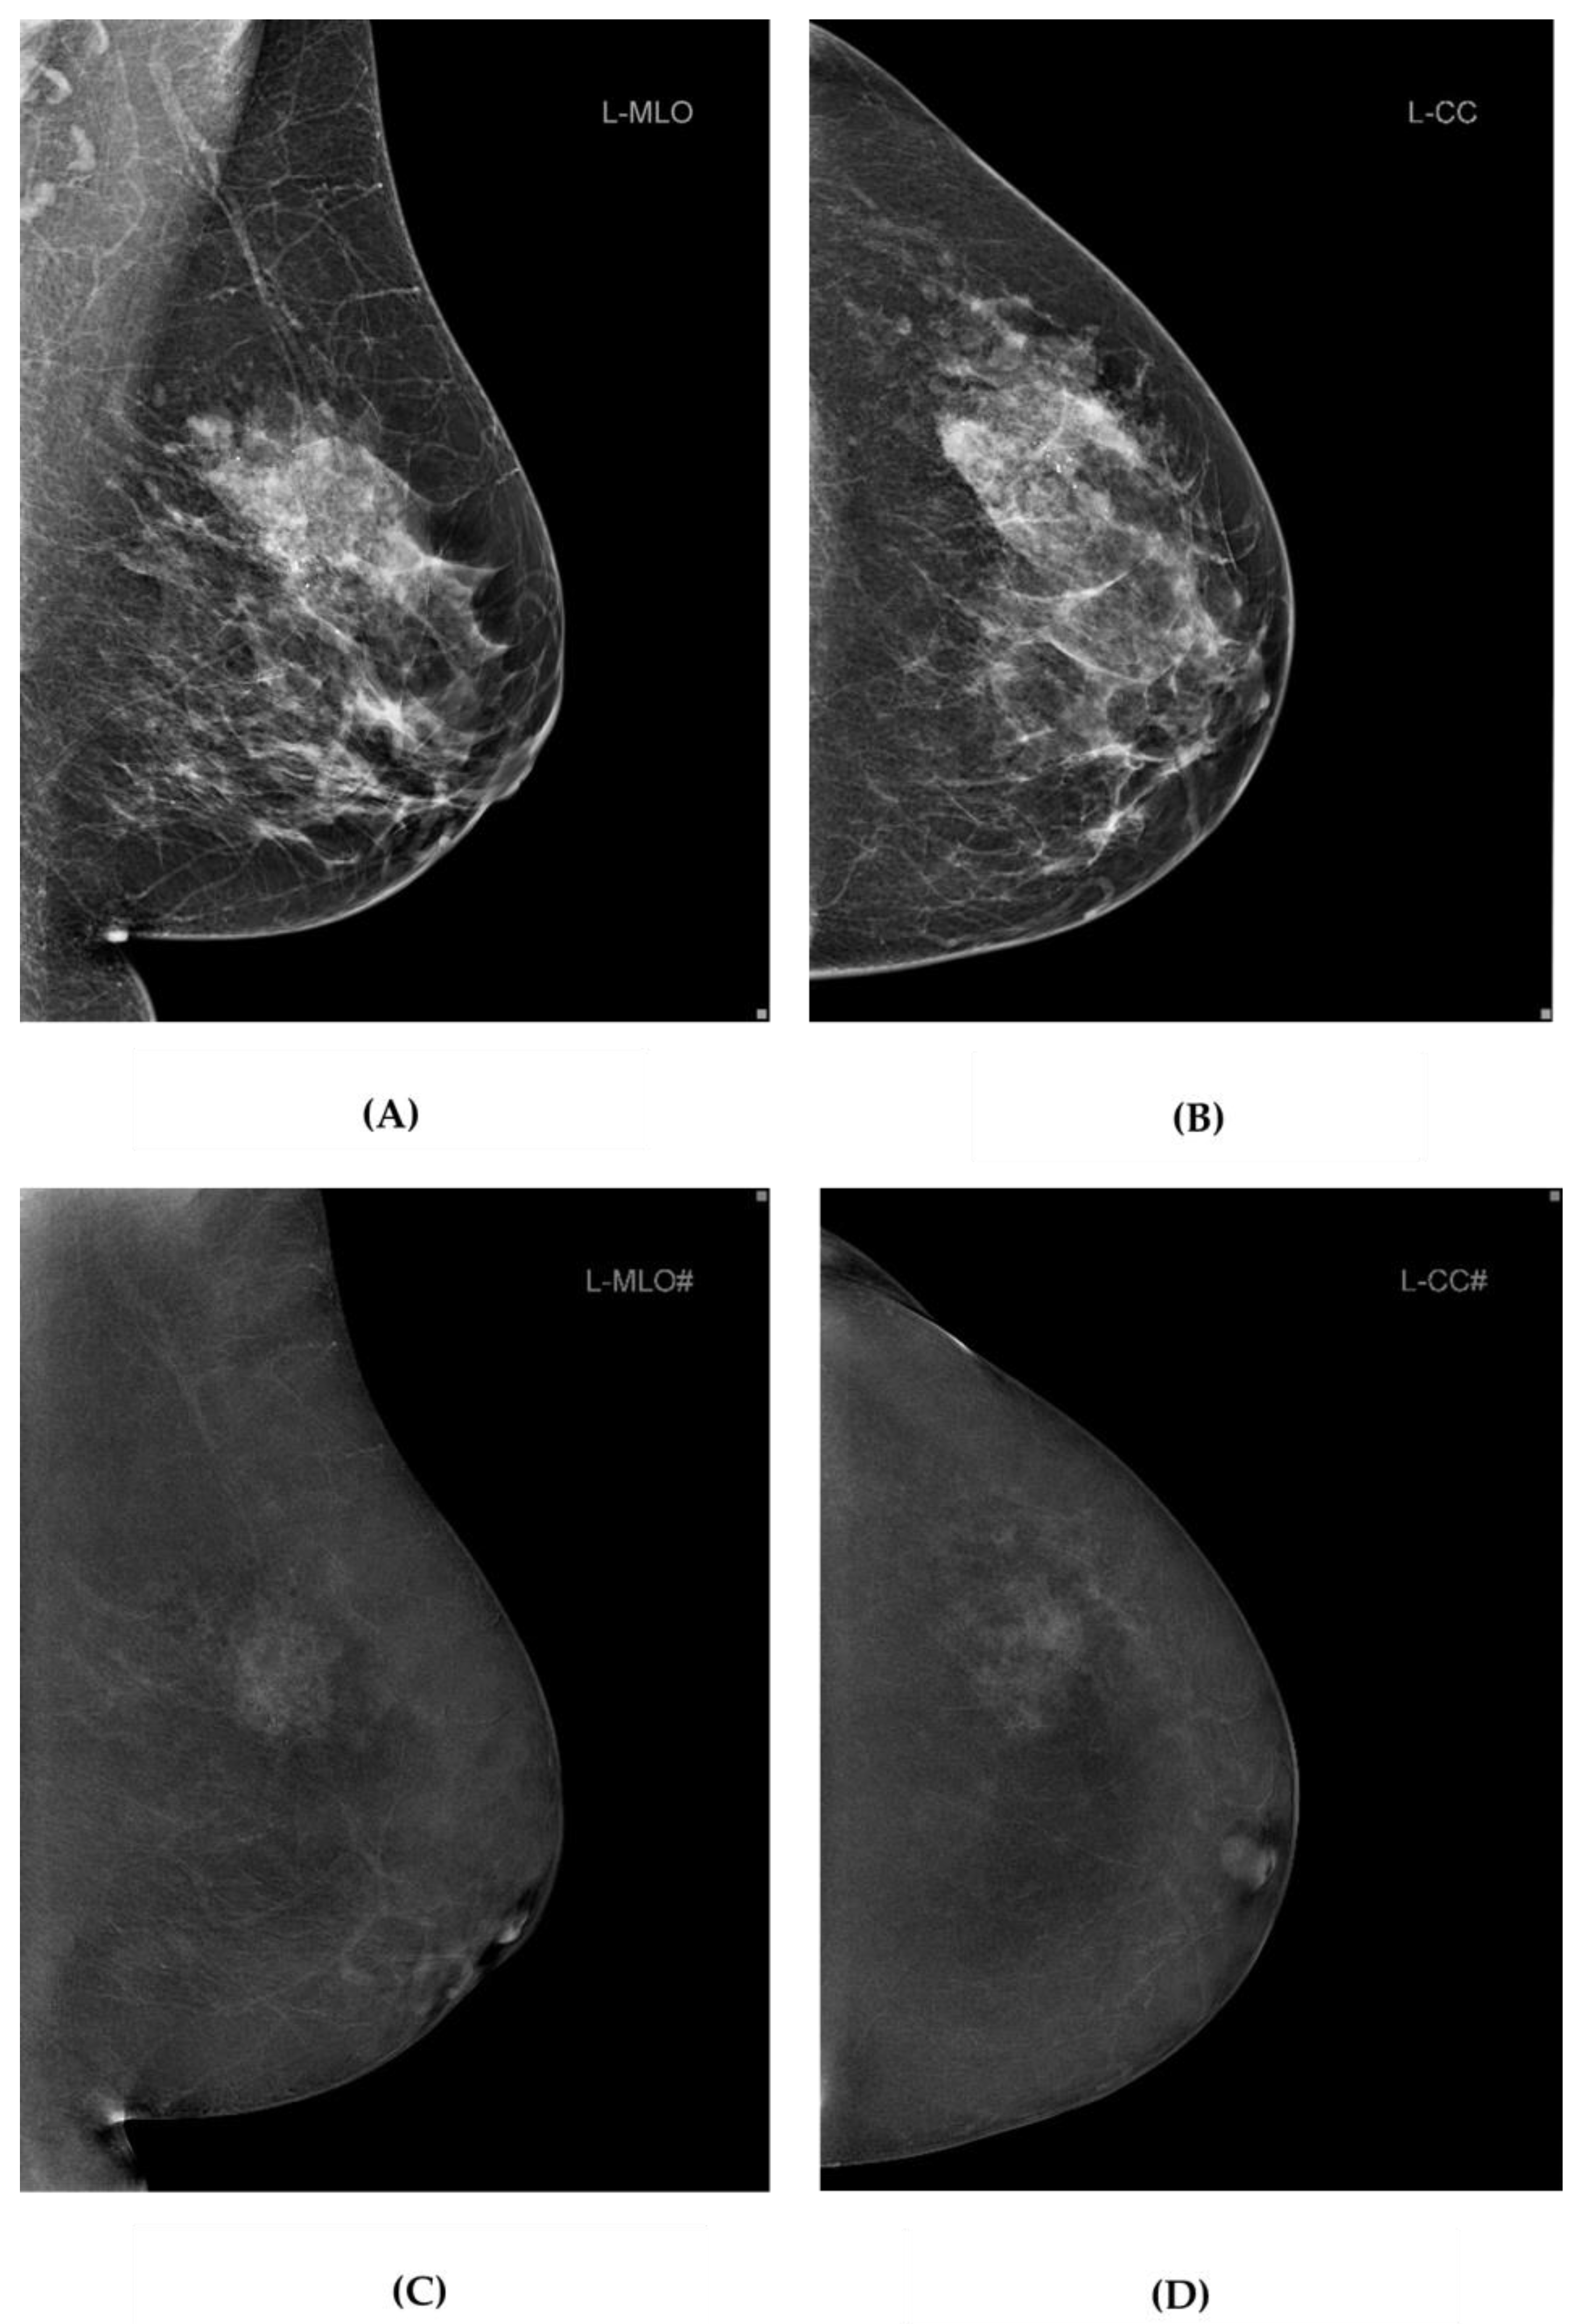

2.3. Image Analysis

Two radiologists with 14 and 5 years of experience in breast radiology independently analyzed MMG and DBT image data as well as CEM image data (Figure 2).

Figure 2. MMG and DBT and CEM image data from our study. Standard MMG (A,B), and CEM (C,D) projections of the left breast of a 63-year-old female participant with breast cancer in UOQ. MMG, mammography; DBT, digital breast tomosynthesis; CEM, contrast-enhanced mammography; UOQ, upper outer quadrant.